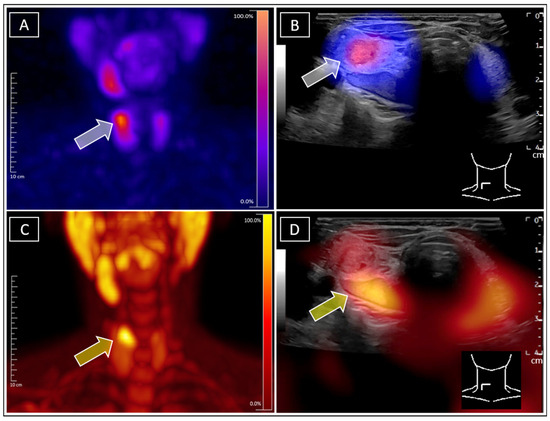

Diagnostic Value of Multimodal Lymphatic Imaging Techniques in Thoracic Duct Outlet Obstruction

Objectives: To investigate the diagnostic value of various lymphatic imaging techniques for thoracic duct (TD) outlet obstruction in patients with chylous leakage. Methods: A retrospective analysis was conducted on 23 patients with chylous leakage who were radiologically diagnosed with a TD outlet obstruction and underwent a TD exploration and reconstruction between January 2022 and February 2025. Non-enhanced magnetic resonance lymphangiography (MRL), 99Tcm-DX lymphoscintigraphy, and intranodal lymphangiography were employed to detect abnormalities in the central lymphatic vessels. The Receiver Operating Characteristic (ROC) curve was utilized to analyze the diagnostic performance of these imaging methods for TD outlet obstruction in lymphatic disorders. Results: Twenty-three patients (fifteen males and eight females) with chylous leakage were included in this study, with an average age of 59.78 ± 13.08 years. Non-enhanced MRL, 99Tcm-DX lymphoscintigraphy, and intranodal lymphangiography revealed TD outlet obstructions in 13, 17, and 18 patients, respectively. Twenty patients exhibited findings consistent with preoperative imaging during TD explorations; the intraoperative microscopic visualization demonstrated the difficulty of white chyle entering the bloodstream for these patients. The ROC curve analysis indicated that “at least two imaging modalities were positive” and had the highest Area Under the Curve (AUC) value (0.90); “intranodal lymphangiography” and “non-enhanced magnetic resonance lymphangiography” followed closely with respective AUC values of 0.76 and 0.73, and 99Tcm-DX lymphoscintigraphy exhibited a lower AUC value 0.63. Conclusions: The combined utilization of multimodal lymphatic imaging techniques demonstrated a high diagnostic accuracy in identifying TD outlet obstruction in patients with chylous leakage. Full article